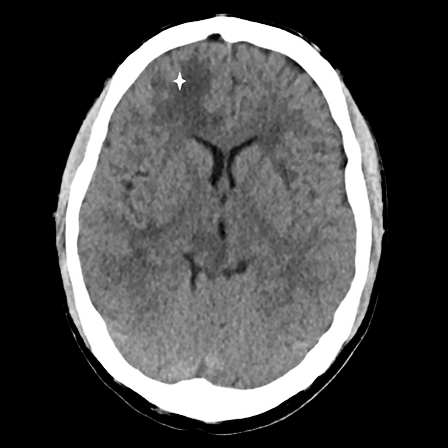

A CT scan of the head without contrast was taken immediately after admission and showed low-attenuation changes in frontal white matter in the right cerebral hemisphere (Fig. 1) and in the right cerebellar hemisphere. Supplementary magnetic resonance tomography of the brain and medulla the following day revealed multiple lesions in the brain stem, cerebellum and both cerebral hemispheres (Fig. 2). The neuroradiologist regarded the findings as consistent with multiple metastases, cerebral tuberculosis, a parasitic disease or septic emboli with secondary abscess formation. Cerebrospinal fluid analysis revealed a leukocyte level of 9 · 109/l, but otherwise normal values for erythrocytes, glucose and protein. The same evening, CT scans of the thorax, abdomen and pelvis were carried out to look for signs of extracerebral disease, including cancer, bacterial infection focus, tuberculosis in or outside the lungs, or signs of a parasitic disease. They revealed multiple micronodules in the lungs, most in the apical parts of both upper lobes, one slightly larger nodule in the apical lateral segment of in the left upper lobe and a small high-attenuation lesion to the right of the entry of the right main bronchus, consistent with a calcified lymph node (Fig. 3). There were multiple low-attenuation lesions in the abdomen and pelvis, most of them in the upper part of the liver, and in addition lesions in the kidneys and prostate. The radiologist described the findings as most consistent with miliary tuberculosis.

Figure 3 CT thorax taken after injection of intravenous contrast medium. The image shows multiple micronodules in the tops…

Figure 3 CT thorax taken after injection of intravenous contrast medium. The image shows multiple micronodules in the tops of both lungs and a 9 mm nodule apically and laterally in the left upper lobe (arrow).